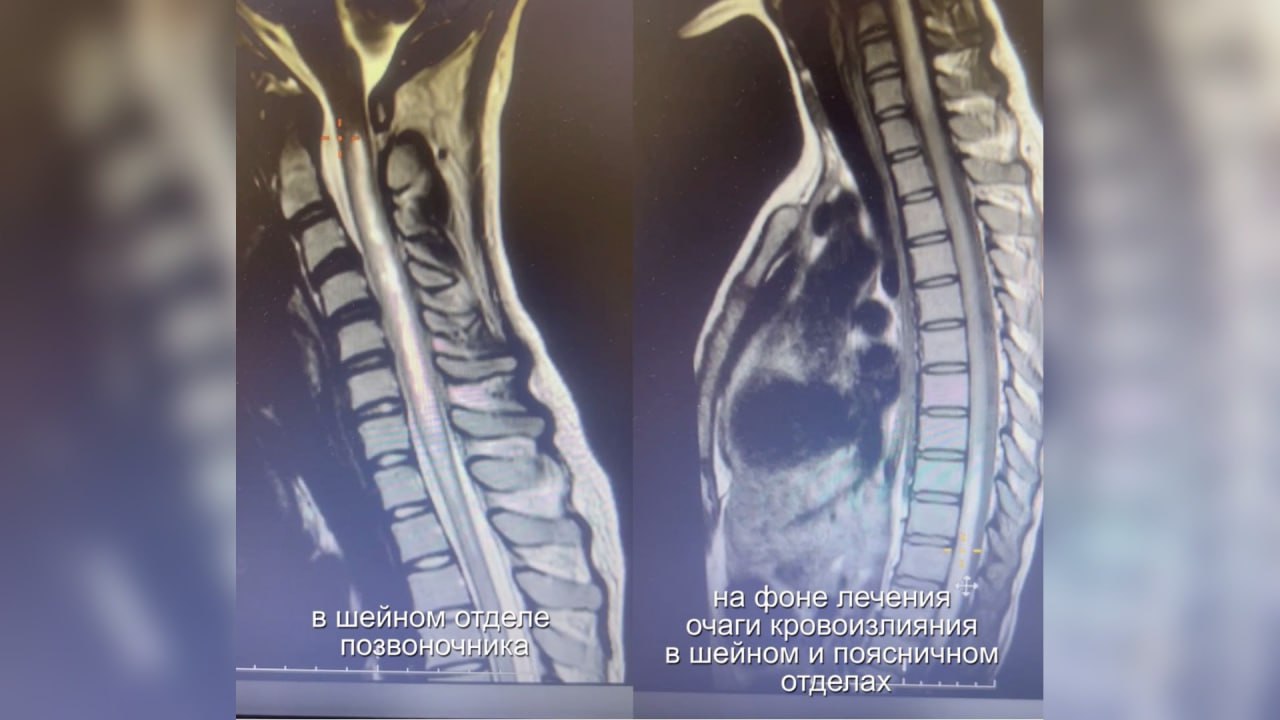

История спасения произошла в БСМП-2 Барнаула. В декабре в больницу поступила 18-летняя девушка. Она пожаловалась на внезапное онемение, слабость в ноге и острую боль в пояснице. Специалисты обнаружили грозный признак, а МРТ подтвердила диагноз — острый поперечный некротизирующий миелит (синдром Фуа-Алажуанина).

Лечение велось под руководством ведущих неврологов больницы и края, включая главного внештатного специалиста Сергея Федянина. Несмотря на новые очаги кровоизлияния в спинном мозге, выявленные на контрольных МРТ, врачам удалось стабилизировать состояние девушки.